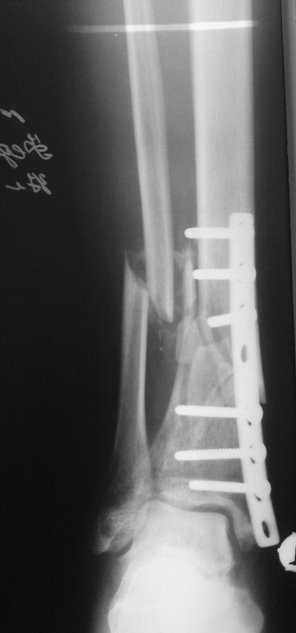

Примерная ситуация. Пациент 37 лет. Синтезировали где-то пластинкой. Попал к

нам через 2 месяца.

19 апреля  убрали через проколы пластину с винтами, пересекли fibula,

наложили аппарат.

Вложение не в текстовом формате было извлечено…

Имя     : 2_preop_lat.jpg

Тип     : image/jpeg

Размер  : 52648 байтов

Описание: отсутствует

Url     : http://weborto.net:8080/pipermail/ortho/attachments/20110817/7ada23a0/attachment-0007.jpg